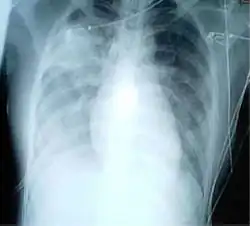

A chest X-ray showing increased opacity in both lungs, indicative of pneumonia, in a patient with SARS

For a case to be considered probable, a chest X-ray must be indicative for atypical pneumonia or acute respiratory distress syndrome.

The WHO has added the category of "laboratory confirmed SARS" which means patients who would otherwise be considered "probable" and have tested positive for SARS based on one of the approved tests (ELISA, immunofluorescence or PCR) but whose chest X-ray findings do not show SARS-CoV infection (e.g. ground glass opacities, patchy consolidations unilateral).[12][13]

The appearance of SARS-CoV in chest X-rays is not always uniform but generally appears as an abnormality with patchy infiltrates.[14]